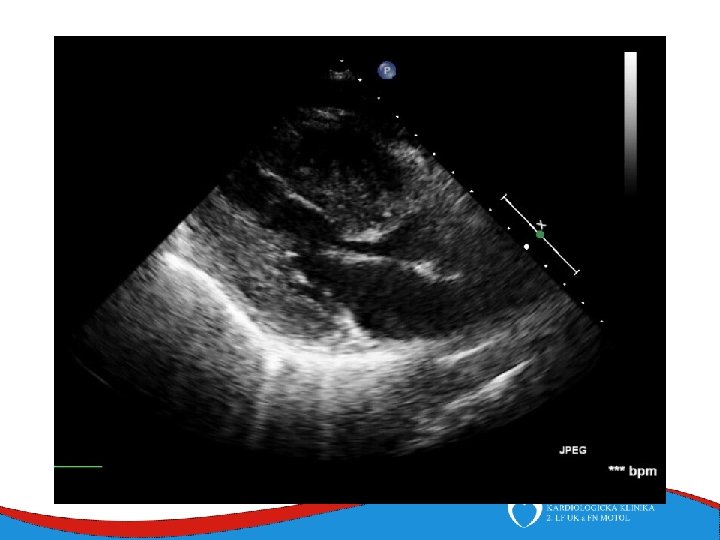

Dilated cardiomyopathy Dilated left ventricle with systolic dysfunction in the absence of coronary ischemia or loading conditions capable of causing such dysfunction (CAD, hypertension, valvular disease, congenital heart disease). Prevalence 1/2 500

Patology and patophysiology Myocytal malfunction (atrophy/hypertrophy) Instersticial fibrosis → impaired systolic and diastolic function → compensatory mechanisms Dilatation (escpecially LV) - diffuse, RV (x CAD) Low CO, congestion Mitral regurgitation, secondary

Signs, symptoms and diagnostics • Heart failure- low CO, congestion • Arrhythmias • Sudden death • SVT, AF- mitral regurgitation- atrial dilatation • Thrombi in left ventricle/ left atrial appendage – CMP • ECG • ECHO – ventricular dilatation and dysfunction • Lab – NT-pro. BNP • Selective coronarography- CAD exclusion • Stress test- prognosis • MRI • EMB– inflammatory CMP